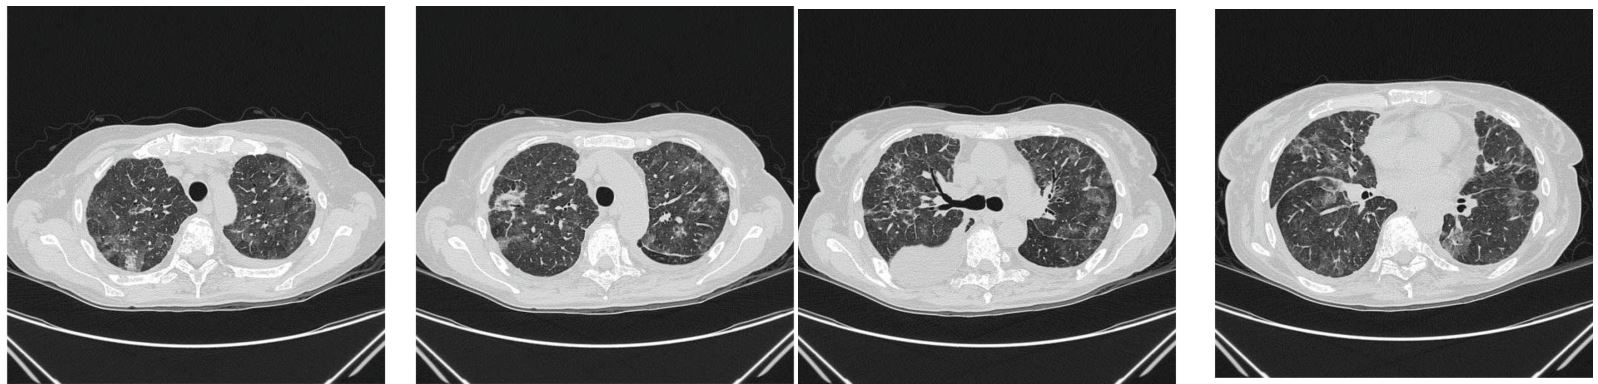

The patient was clinically better, but the control radiographic finding was in progression. Therefore, a pulmonologist was involved. Blood gas analyzes were: pH 7.47↑, pCO2 4.1↓, pO2 7.3↓, cNa +135↓, cK +3.2↓, cCa + 1.14↓, glucose 5.2, Lac 3.5, cHct 35, cHCO3 22.6, SO2 c 90%. Laboratory analyzes showed the control values in the Table 1. The ionogram was within the acceptable limits of the reference values. The urine test was normal. Immunological analyzes were within the limits of reference values: IgG 8.44 g/L, C3 1.59 g/L, C4 0.55 g/L, RF 11 IU/ml, AMA 1.1 IU/ml, ds DNA 10.2 IU/ml, cANCA 1.2 IU/ml, pANCA 0.9 IU/ml, ANA DETECT 0.3 (index). Tumor marker values were: CEA 474.1 (the limit values <5 ug/L) and CA 15-3 19899 (the limit values <23.5 U/ml). The pulmonologist prescribed corticosteroid therapy according to the following scheme: 40 mg of prednisone once daily for 3 weeks, then 30 mg of prednisone once daily for a month, then 20 mg of prednisone once daily for 3 months. Other recommended therapy by the pulmonologist included: PPI, LMWH, dual antibiotic therapy with a probiotic, formoterol/beclomethasone spray 100/6 mcg 3 times for two inhalations, fenoterol/ ipratropium bromide spray 3 times for two inhalations, oxygen therapy 1.5-2 l per minute, 18 hours during the night and day. After 3 months of therapy by a pulmonologist, the patient underwent a control scan of the chest and abdomen, which described a complete regression of zones according to the type of GGO as part of ILD/pneumonitis (Figure 3). The latest laboratory results are displayed in the third column of the Table 1. Tumor marker values then were: CEA 101.5 (the limit values <5 ug/L) and CA 15-3 3786 (the limit values <23.5 U/ml).

Figure 3: CT scan with complete regression of zones according to the type of GGO as part of ILD/pneumonitis.

The patient was presented to the consilium, which now makes the decision that the patient should continue with Arimidex and report in 3 months with the control findings of the chest and abdomen scanner. Other findings are stationary compared to the previous chest scanner.

In the MONARCH 3 trial, which compared the combination of abemaciclib and an aromatase inhibitor to an aromatase inhibitor alone in untreated postmenopausal women with HR-positive, HER2-negative locoregionally recurrent or metastatic breast cancer, one patient treated with the combination died from pneumonitis. In the MONARCH 2 trial, which compared the CDK4/6 inhibitor + fulvestrant to fulvestrant alone in women with HR-positive, HER2-negative advanced or metastatic breast cancer who have disease progression following endocrine therapy, two patients died from pneumonitis. The MONARCH 2 trial’s results supported the approval of abemaciclib [11]. According to the prescribing information, cases of interstitial lung disease/pneumonitis were also reported after approval [12]. Ribociclib in combination with an aromatase inhibitor was also approved in 2017 as initial endocrine-based therapy for postmenopausal women with HR-positive, HER2-negative advanced or metastatic breast cancer [11]. There is less evidence showing the link between CDK-4/6 inhibitors and pulmonary toxicity. The articles on pablociclib- and abemaciclib-induced lung injury illustrate the potentially fatal drug-associated lung injury that may be associated with them. After four weeks of ribociclib use, our patient developed pneumonitis, which is uncommonly reported in the medical literature. The multi-slice chest scan revealed ILD/pneumonitis with GGO-type zones that were highlighted on both sides in the upper lobes and the lower left lobe, as well as bilateral pleural effusion (Figure 1). The clinical findings were worse than the radiographic (Figure 1). Therefore, ribociclib was discontinued along with starting methylprednisolone (1.5 mg/kg/day), with noticeable clinical improvement within 1 week. Six week later a control CT chest scan displayed progression of the previously described zones in the lung parenchyma according to the type of GGO (Figure 2). The patient was clinically better, but the control radiographic finding was in progression. Therefore, the pulmonologist prescribed corticosteroid therapy according to the following scheme: 40 mg of prednisone once daily for 3 weeks, then 30 mg of prednisone once daily for a month, then 20 mg of prednisone once daily for 3 months. After 3 months of therapy by a pulmonologist, the patient underwent a control scan of the chest and abdomen, which described a complete regression of zones according to the type of GGO as part of ILD/pneumonitis (Figure 3). In addition, previous real-world study based on the FAERS database showed that a median latency of 63 days (range 21-136) for CDK4/6 inhibitor-associated ILD [1]. This finding was in line with the results from an adverse event-time analysis of abemaciclib and palbociclib using data from Japanese Adverse Drug Event Report (JADER) database, suggesting that both abemaciclib and palbociclib were associated with the onset of ILD after 1-2 months from the start of treatment [29]. A retrospective study of drug-induced ILD demonstrated that, there was a certain similar trend in the timing of the occurrence of ILD induced by most anticancer drugs, most of which occurred within 3 months [30]. There are no known risk factors for the development of lung inflammation associated with CDK4/6 inhibitor use [11]. For patients with severe interstitial lung disease and/or pneumonitis who develope new or worsening pulmonary symptoms, the FDA recommends interrupting treatment and permanently discontinuing CDK4/6 inhibition and initiating corticosteroids [26]. It is essential for clinicians to remember that fatal interstitial pneumonitis can occur in ribociclib-treated patients (even after only four weeks into treatment), as early diagnosis can be crucial [9]. Besides early diagnosis of ILD/pneumonitis proper and continuos usage of corticosteroids is also crucial.